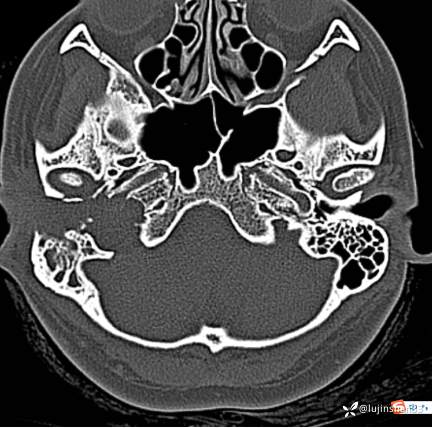

颞骨CT: